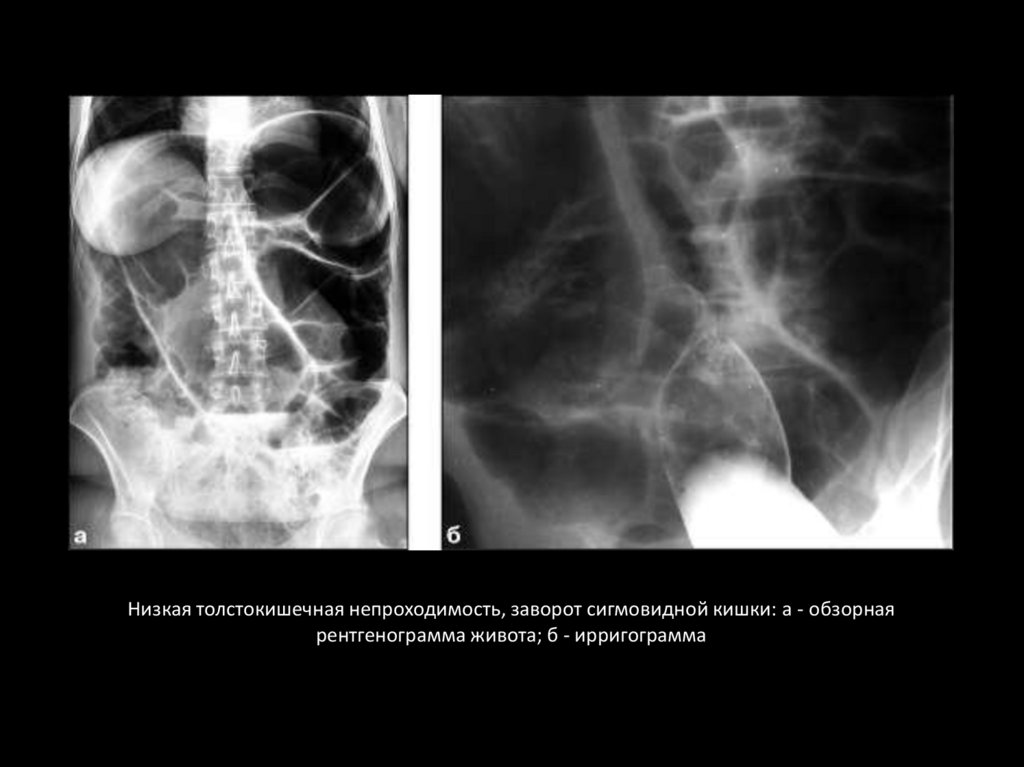

Низкая толстокишечная непроходимость, заворот сигмовидной кишки: а - обзорная

рентгенограмма живота; б - ирригограмма